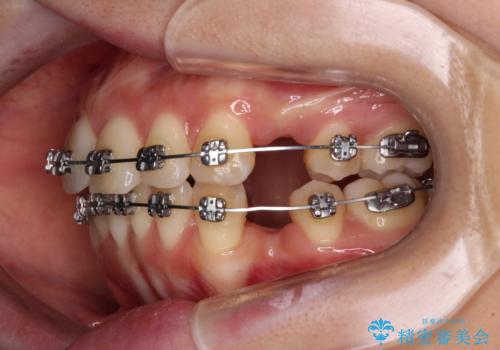

- メタルブラケット

- 治療期間

- 2年2ヶ月

上下ともに歯列が前方に突出していたため、上下左右の第一小臼歯4本を抜去し、ワイヤー装置による矯正治療を行うこととしました。